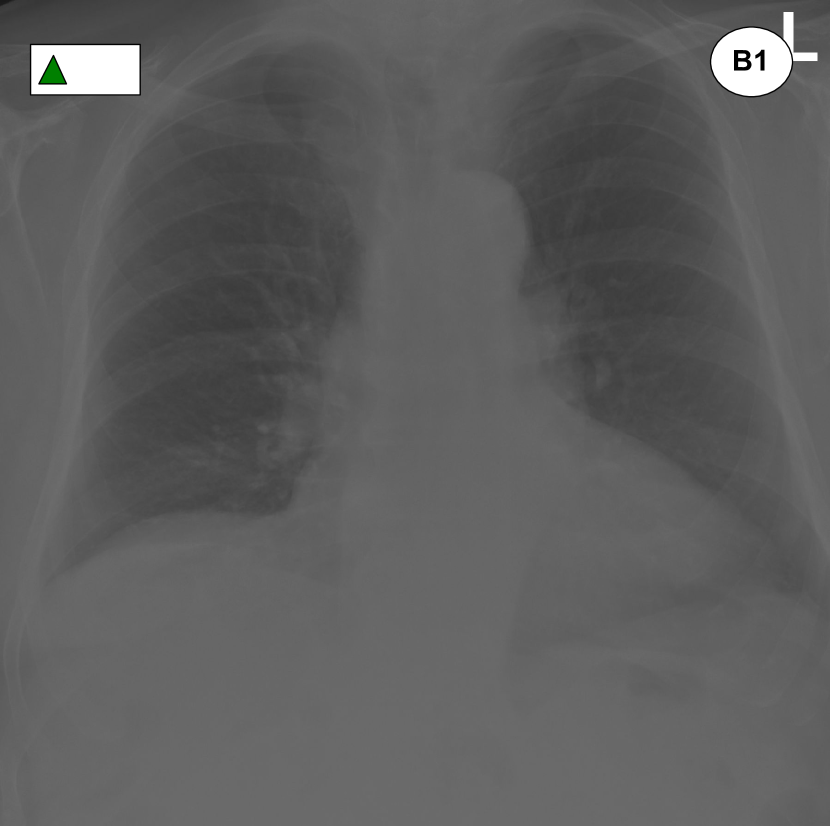

Figure 1: Examples of pairs of images that are placed close to each other in the learned embedding space shown in Fig. 3. A1 was incorrectly reported, but a second reading shows the presence of pleural effusion and a medical device, which justifies its proximity to A2. B1 was labelled as “normal”, but a second reading reveals some degree of cardiomegaly and, as such, the scan is placed close to B2. An extract from the original reports can be found under each image. Fig. 3 contains the legend for the labels.

Figure 3 shows a 222-dimensional representation of the 2,25222522,252 radiographs contained in the Golden Set. This representation was obtained by means of dimensionality reduction using a t𝑡t-distributed Stochastic Neighbor Embedding (t-SNE) [16], which effectively projects the 646464-dimensional embeddings extracted from the best model onto 222 dimensions for visualisation purposes. Remarkably, this projection shows that the normal exams are mostly concentrated in a well-separated cluster; moreover, other clusters of exams sharing similar abnormalities have also been identified.

The chest radiographs marked with a circle can be seen in Figure 1. These are two examples of radiographs that were originally labelled as normal but ended up being placed away from the cloud of normal exams. A second reading of these exams has revealed unreported abnormalities thus confirming that their position within the embedding was justified.

Figure 3: 222-dimensional embedding of all chest radiographs contained in the golden dataset learned through the ML2+ loss and visualised via multi-dimensional scaling. Each exam is represented as a point with different shapes and colors to identify multiple labels. Well-separated cluster of “normal” radiographs (green triangles) and exams featuring an enlarged heart are clearly visible. See Fig. 1 for the circled images.